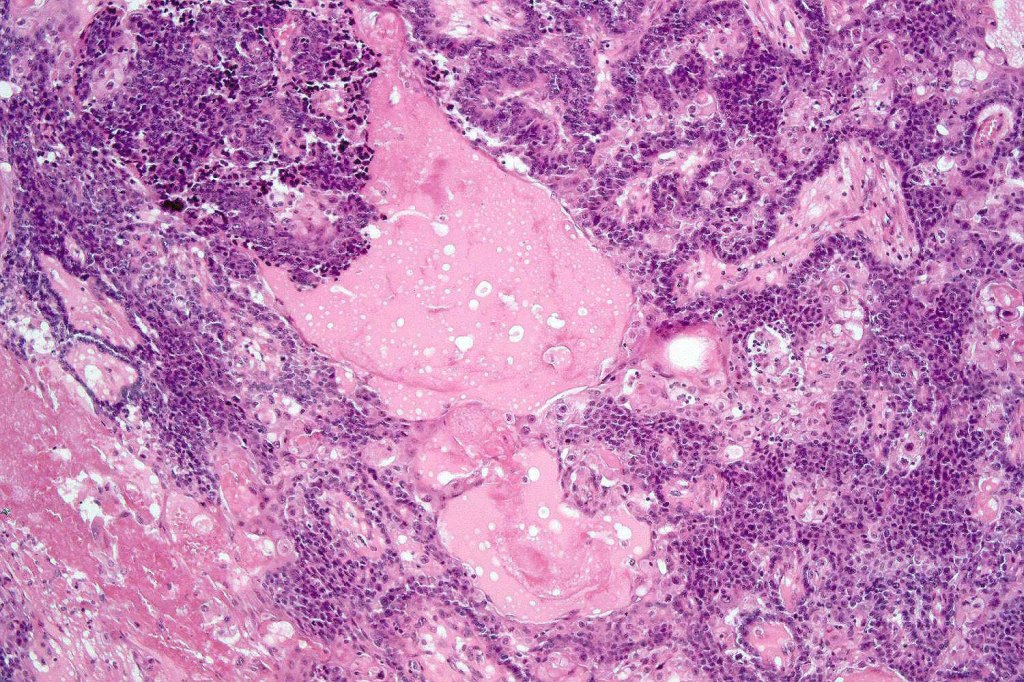

•Well differentiated lobular growth pattern though to a poorly differentiated tumor often showing a diffuse, infiltrating border which may extend into the subcutaneous fat

•Comedo type necrosis commonly present

•Tumors are composed of an admixture of darkly staining basaloid cells with hyperchromatic or vesicular nuclei and more obvious sebaceous cells with eosinophilic, bubbly, multivacuolated cytoplasm frequently indenting the nucleus (scalloped)

•Focal squamous differentiation with keratinization can be present resulting in confusion with squamous cell carcinoma

Sebaceous carcinoma from a patient with Muir-Torre syndrome kindly shared by Dr. Antonina Kalmykova.